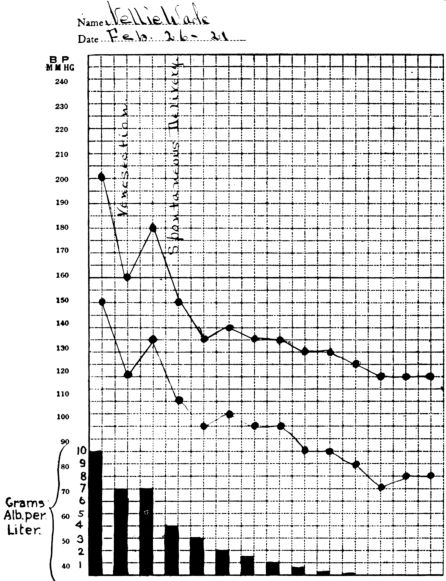

| 1. | Showing drop in blood pressure and albumen, after delivery, in eclampsia | 204 |